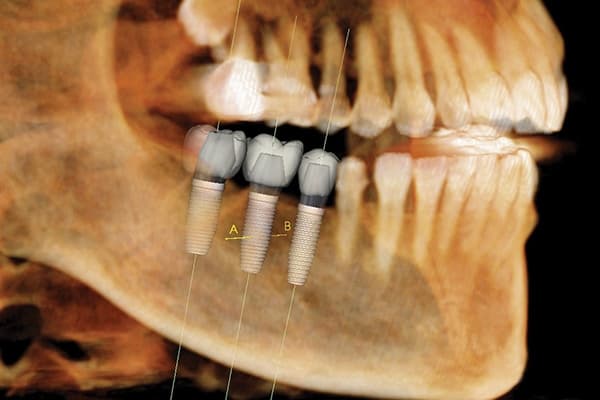

A dental CT scan is a type of X-ray that produces 3D images of the teeth, jaws, and surrounding structures. This technology is particularly useful in surgical planning for dental implants, as it can provide detailed information on bone quality and nerve canals. Unlike traditional X-rays, which only show a flat image of the teeth and jawbone, a CT scan provides a more detailed and accurate picture of the area.

Dental CT scans are necessary for a variety of reasons. For example, they can help diagnose and treat conditions such as impacted teeth, cysts or tumors, bone defects, or nerve canal involvement that could affect treatment. They are also useful in planning for dental implants, root canals, wisdom teeth extractions, and orthodontic treatments such as braces or Invisalign.